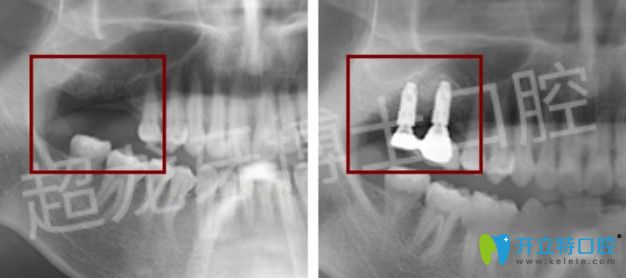

種植案例:

長春超龍牙博士口腔多顆牙種植案例圖

牙齒情況:多顆牙缺失

種植技術(shù):微創(chuàng)無痛種植技術(shù)